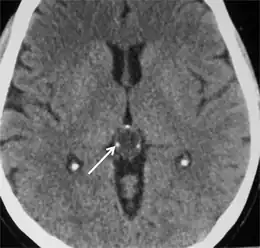

Pineocytoma in a 35-year-old person